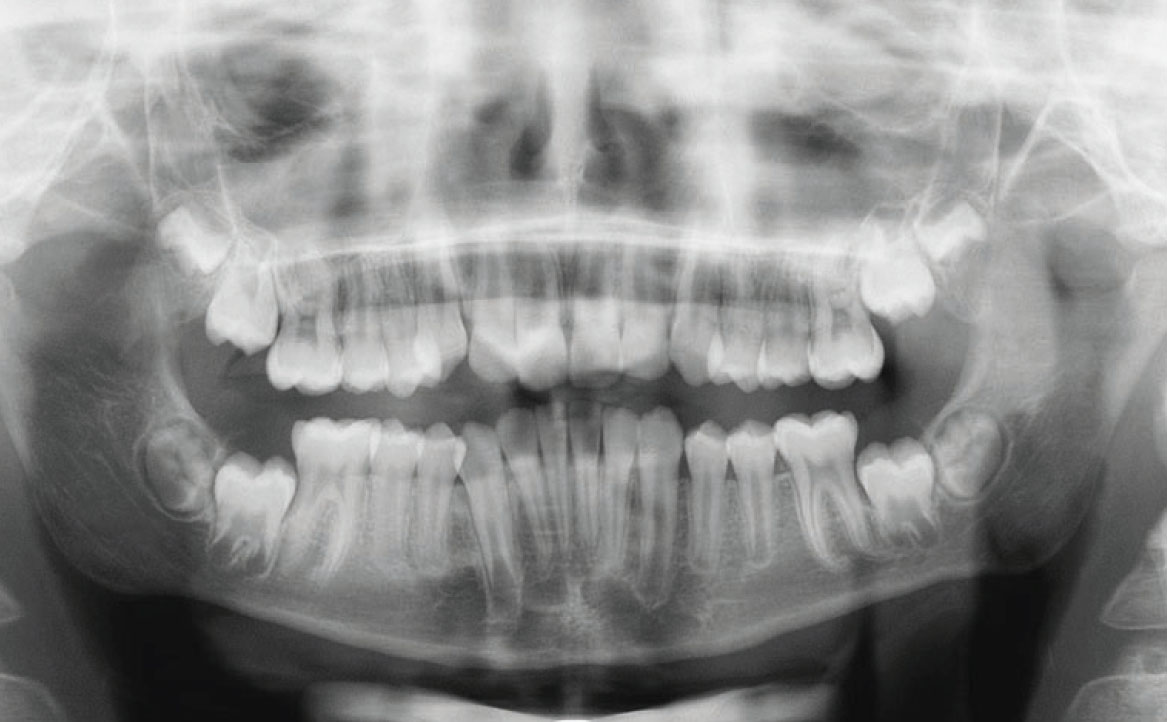

Tale affermazione è stata dimostrata dall’analisi dell’ortopantomografia, in cui era evidente la presenza di materiale non riassorbile, presumibilmente materiale di otturazioni canalari per elementi definitivi, utilizzato in questo caso clinico in elementi dentali decidui, con conseguente difficoltà nel processo di esfoliazione e riassorbimento delle radici stesse (fig. 1).

Terminata la prima fase, all’età di 11 anni, il paziente è stato rivalutato tramite gli esami radiografici. Dall’OPT si osservava la presenza della dentatura permanente, con prossima esfoliazione dei settimi, oltre alla formazione delle gemme degli elementi 18-28-38-48 (fig. 4).

La teleradiografia latero-laterale confermava il sospetto di una seconda classe scheletrica, con angoli SNB e ANB rispettivamente di 77° e 5°, con un aumento della pro-inclinazione degli incisivi superiore e un aumento dell’overjet, corrispondente a circa 6 mm (fig. 6).